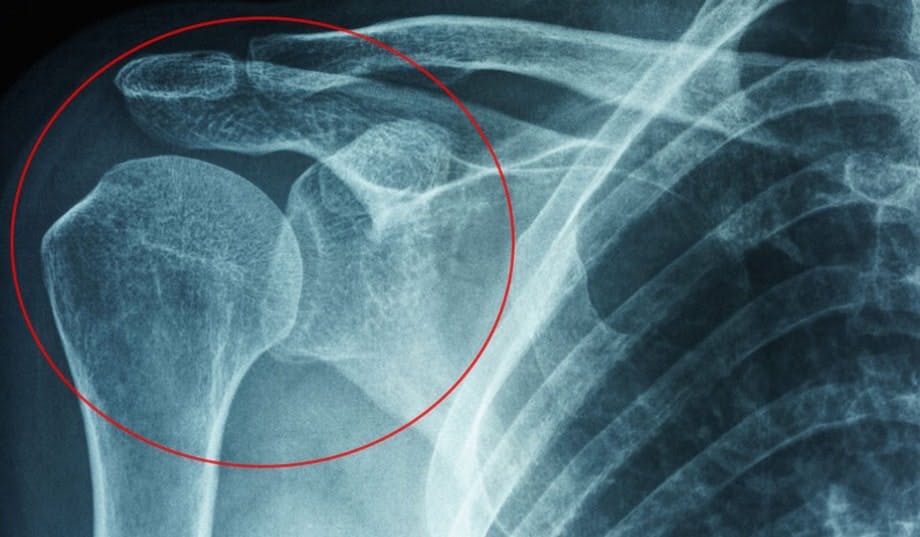

Overarmsknokkelen er festet til skulderbladet i et ledd som holdes på plass av en kapsel fylt med bindevev. Ved frossen skulder oppstår det en slags betennelse i denne leddkapselen, og bindevevet blir stivt. Samtidig vokser det ut unormalt vev, og produksjonen av smørende leddvæske hemmes. Det går drastisk ut over bevegeligheten og fører til smerter.

FROSSEN SKULDER Overarmsknokkelen er festet til skulderbladet i et ledd som holdes på plass av en kapsel fylt med bindevev. Ved frossen skulder oppstår det en slags betennelse i denne leddkapselen, og bindevevet blir stivere og strammere.